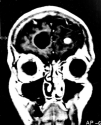

Fig. 2. Resonancia magnética nuclear cerebral.